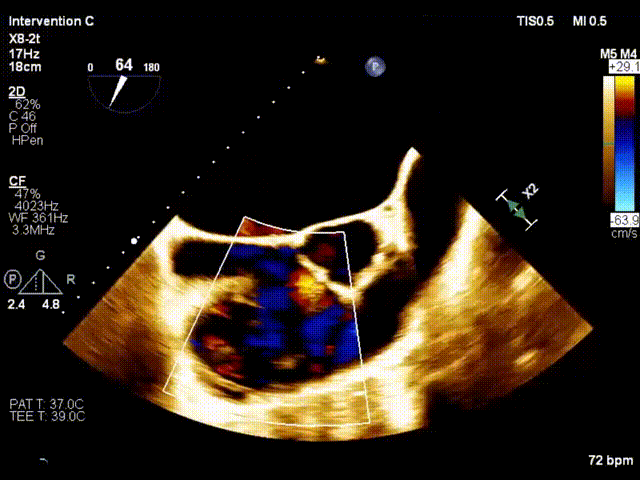

术前超声

术后超声